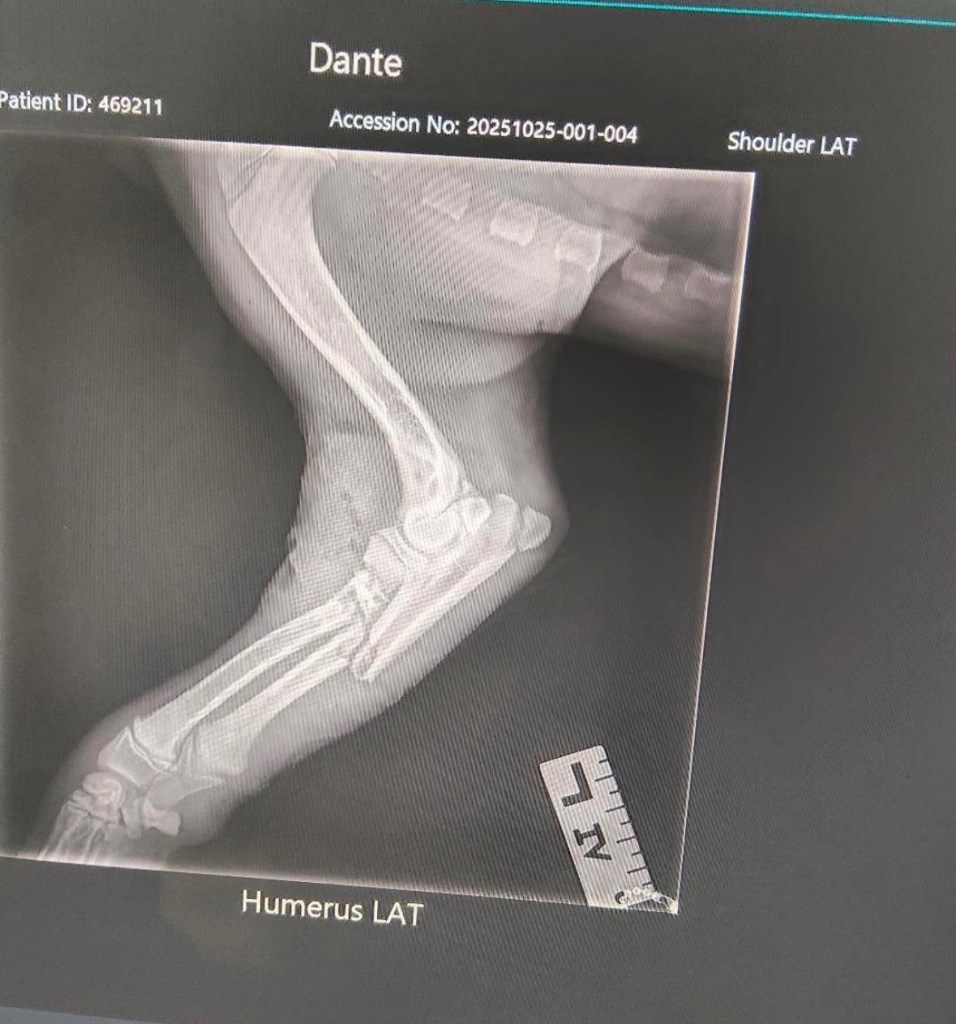

A family takes their young children and new puppy to a public dog park, a space meant for community, connection, and safe recreation. Within seconds, their puppy is mauled by an off leash “American Staffy,” a common pit bull type breed. The attack lasts 4 minutes. Their puppy’s leg is shattered. Their children witness it all. The owners of the attacking dog flee accountability.